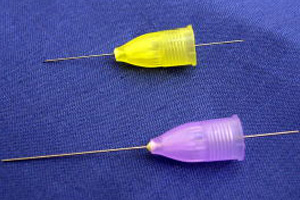

痛みに敏感な方でも安心して治療を受けられるよう、当院では「表面麻酔」と「極細の針」を組み合わせて、できるだけ痛みを抑える工夫を行っています。

2.「極細の針」を使用

針が細ければ細いほど痛みは少なくなります。当院では極細の針を使い、ソフトに注射することで痛みを抑えます